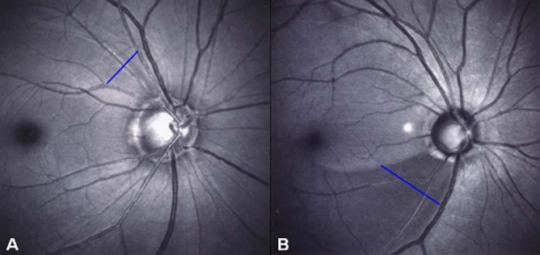

Retinal nerve fiber layer defect